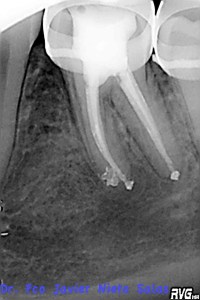

Se citó a revisión a los nueve meses, no presentaba sintomatología y los signos claros de evolución positiva.

Hola Cecilia, muchas gracias por entrar en el blog y opinar, con respecto al tema de los movimientos ortodóncicos y las lesiones periapicales, existe un articulo bastante interesante en el JOE del 2006, «Influence of Orthdontic Dental Movement on the Healing Process of teeth With Periapical Lesions», donde se dice que no impide el proceso de reparación, pero que quizás pueda retrasarlo.